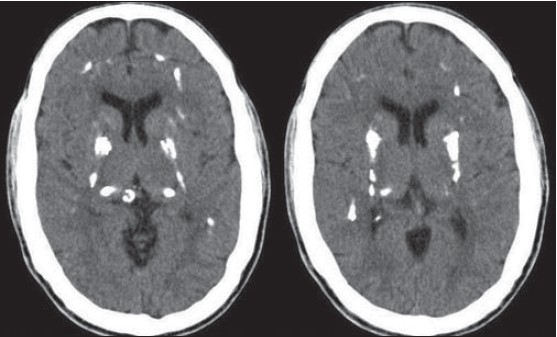

Istraživanjima je do sada utvrđena veza između kalcija kao dodatka ishrani i povećanog rizika od ishemijskog moždanog udara, a koja ukazuje na to da uzimanje dodatnog kalcija doprinosi arterijskoj kalcifikaciji, uglavnom u masnim naslagama koje potiču blokiranje krvnih žila. Time dolazi do smanjenog protoka krvi te manje količine kisika (ishemija) zbog čega dolazi do lezija na mozgu. Drugi način na koji kalcij može imati izravan neurotoksični učinak na mozak je ulazak viška kalcija u moždane stanice, što dovodi do stanične smrti.

Otkriveno je da je korištenje prehrambenih dodataka za starije odrasle osobe koji sadrže Ca [kalcij] povezano s većim brojem lezija na mozgu, čak i nakon uspostavljanja kontrole nad uobičajenom količinom unosa Ca. Zanimljivo, ni količina dodatnog Ca niti trajanje dodatnog Ca nije se povezivalo s količinom lezija. Ova otkrića ukazuju da dodatni Ca ima nepovoljne biokemijske učinke kod starijih osoba bez obzira na dozu. – piše u studiji.